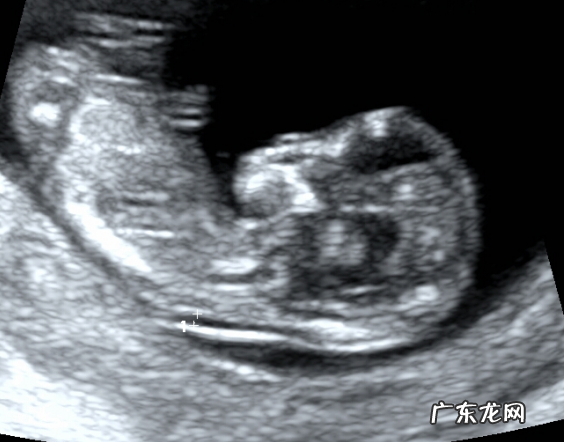

上图就是一个两脚朝天 , 此时我们可以在这个切面观察TA 的股骨长 , 股骨长的测值也可以作为矫正孕周的一个重要参数 。